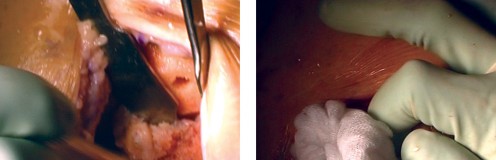

The distal femoral resection is typically performed first, utilizing an intramedullary alignment guide. The entry hole is made just anterior to the origin of the PCL. The valgus angle of the cutting block is set based on preoperative templating (usually 5 to 7 degrees) to restore a neutral mechanical axis. The distal cut removes approximately 9 mm of bone from the most prominent condyle, corresponding to the thickness of the femoral component.

Next, the proximal tibial resection is executed, almost exclusively using an extramedullary alignment guide. The guide is aligned with the medial third of the tibial tubercle proximally and the center of the talus distally. The cutting block is set to resect 8 to 10 mm of bone from the unaffected compartment, incorporating a 3 to 5-degree posterior slope. This cut must be strictly orthogonal to the mechanical axis of the tibia in the coronal plane.

Femoral sizing and rotation are then determined. Proper femoral rotation is paramount for patellofemoral tracking and flexion gap symmetry. The rotation is typically set at 3 degrees of external rotation relative to the posterior condylar axis (PCA), or parallel to the surgical transepicondylar axis (TEA) and perpendicular to Whiteside's line (the AP axis of the trochlea). Once rotation is established, the anterior, posterior, and chamfer cuts are made using a 4-in-1 cutting block.